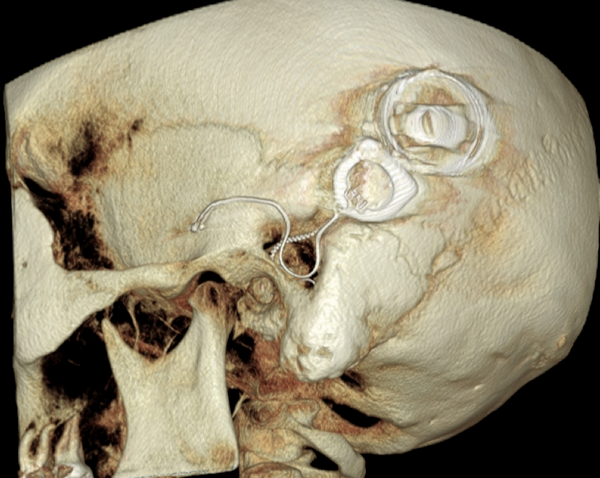

Both patients were imaged immediately with CBCT using SCANORA® 3Dx (Soredex, Tuusula, Finland). The field of view (FOV) was 140 x 165 mm and voxel size 0.2 mm. Imaging parameters were 90 kV, 8 mA, 4.00s. Standard 1 mm axial, coronal and sagittal reformations were made, as well as MIP and 3D reconstructions using OnDemand3D™ software (Cybermed, Seoul, South Korea).

CBCT proved to be optimal for imaging of these implants because of the superior bony delineation and nearly artefact free images. All four parts, i.e. the receiver stimulation part, extracochlear electrode implanted on the surface of the temporal bone, the extracochlear electrode plate and the intracochlear electrode array could be well imaged with CBCT.

On CBCT all four of the important parts of the implant were very well seen both on the axial slices and three dimensional surface reconstruction images. The implant is placed on magnetic plates, and the extracochlear part was seen in an abnormal separated position. The intracochlear electrode array showed no signs of separation in either of the cases. The intracochlear electrodes were well seen in both of the cases.

The optimal images of these two patients are shown in the radiographic illustrations in Figures 1-7.

Figure 3: 3D reconstruction image of patient 1.